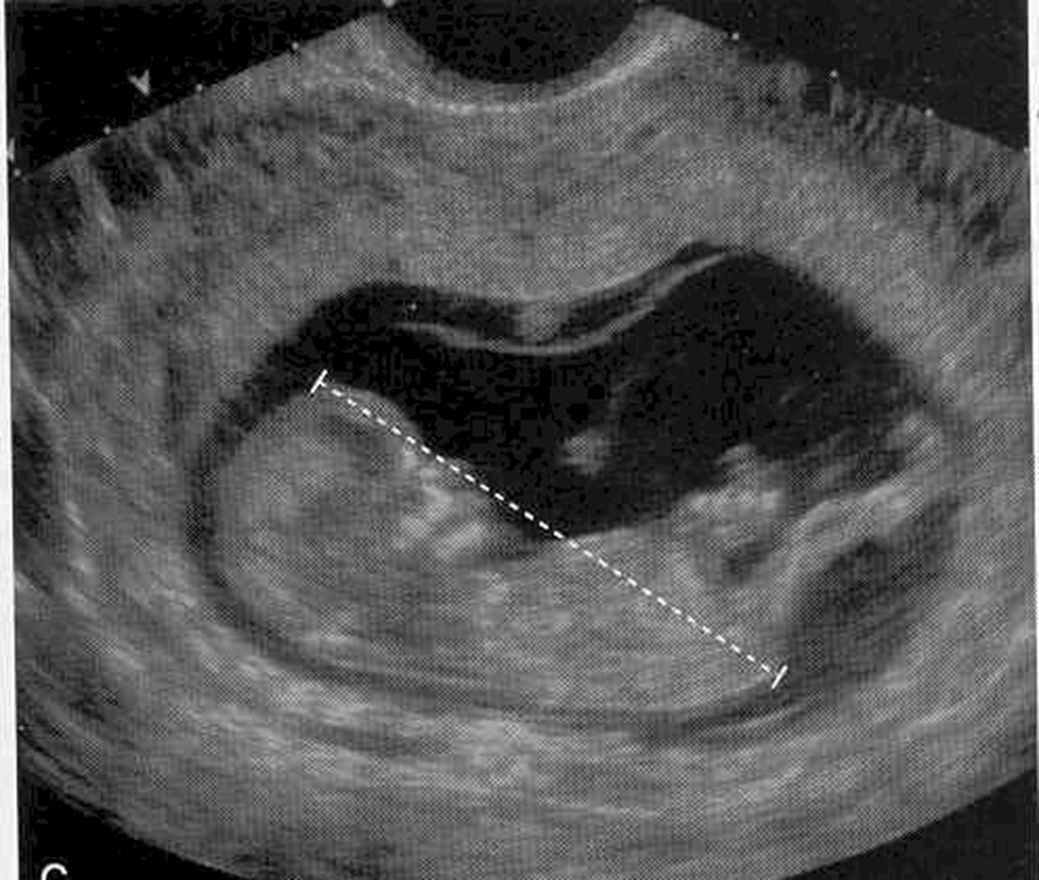

What is the most accurate way to date pregnancy?

crown rump length

CRL is typically done up to ____weeks

12 (can be done up to 14 weeks)

Cardiac activity should definitively be seen in a CRL measuring

5-7 mm